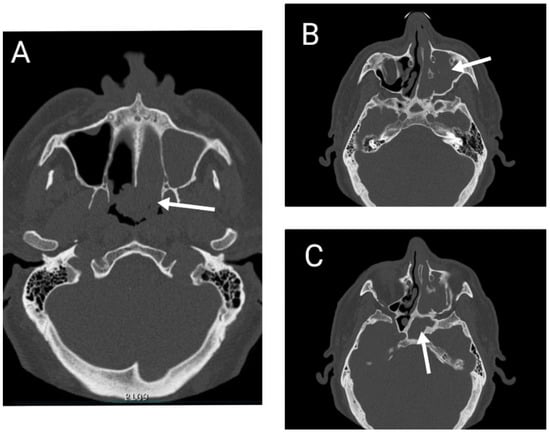

A computed tomographic scanning of the head and paranasal sinuses was performed, showing extensive parafluid-solid densities completely occupying the left maxillar, ethmoidal, sphenoidal sinuses and the entire left nasal cavity, expanding in the nasopharynx through the left choana. (Figure 2).

Figure 2. CT scan of the head and paranasal sinuses showing tumor extension in the (A) nasal cavity, nasopharynx, and contralateral choana, (B) maxillary sinus, (C) sphenoidal sinus.